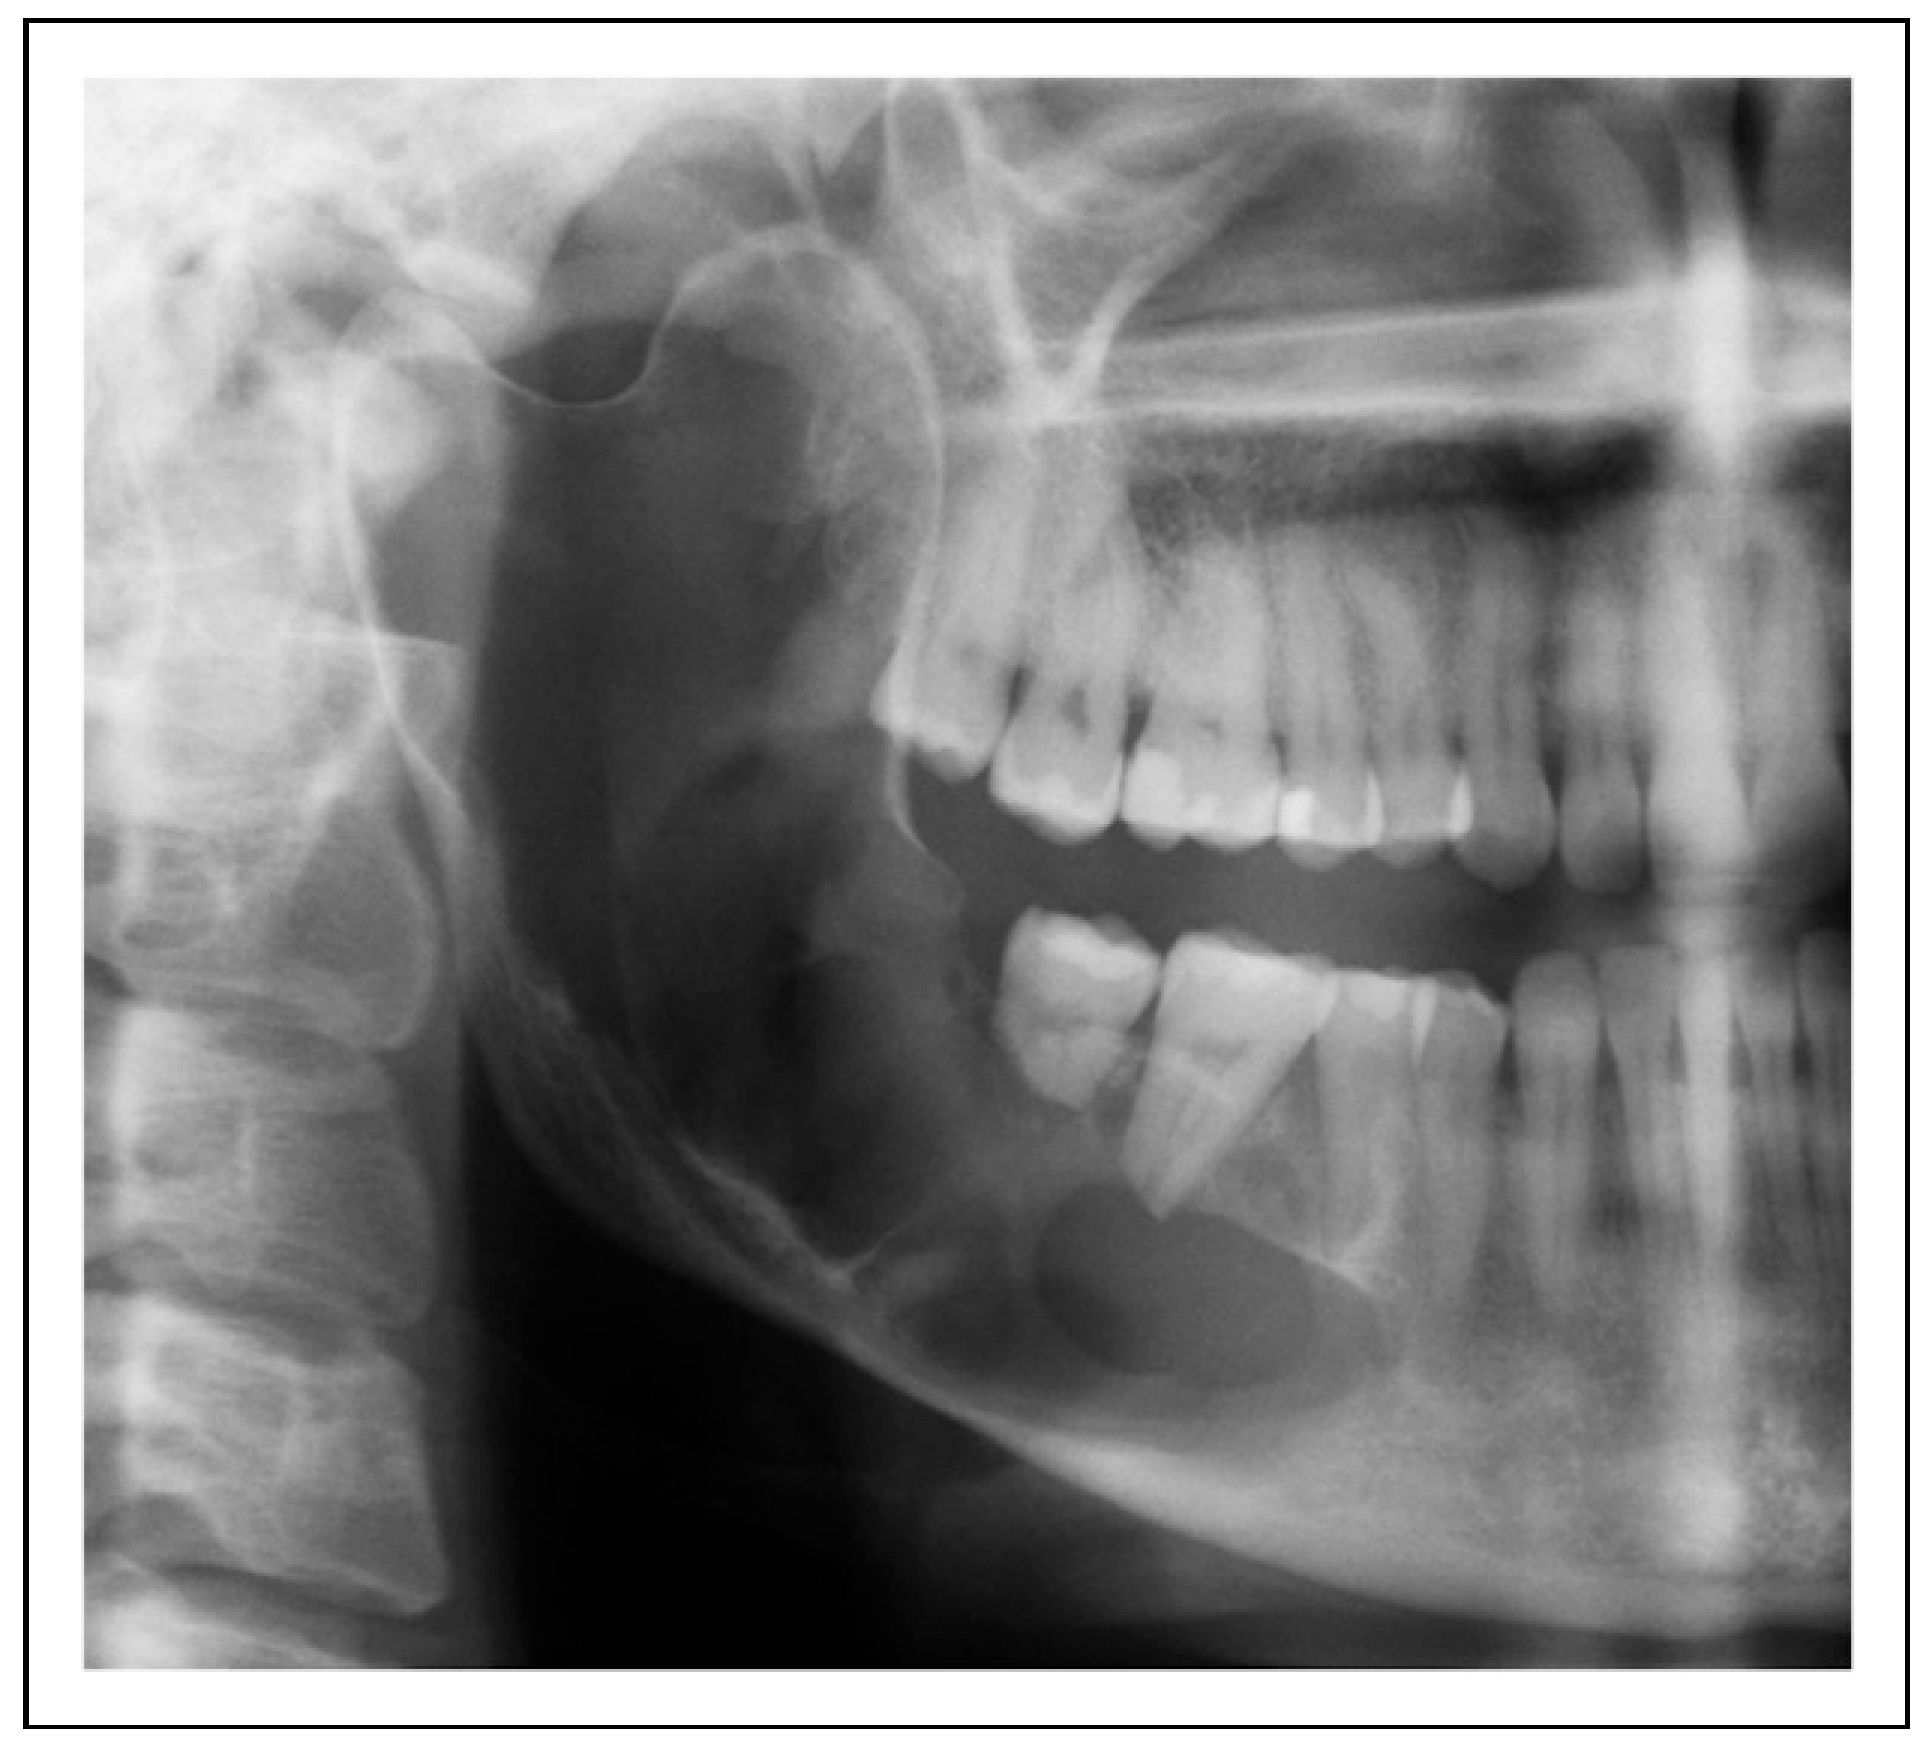

Two-Stage Regime, Patient 1